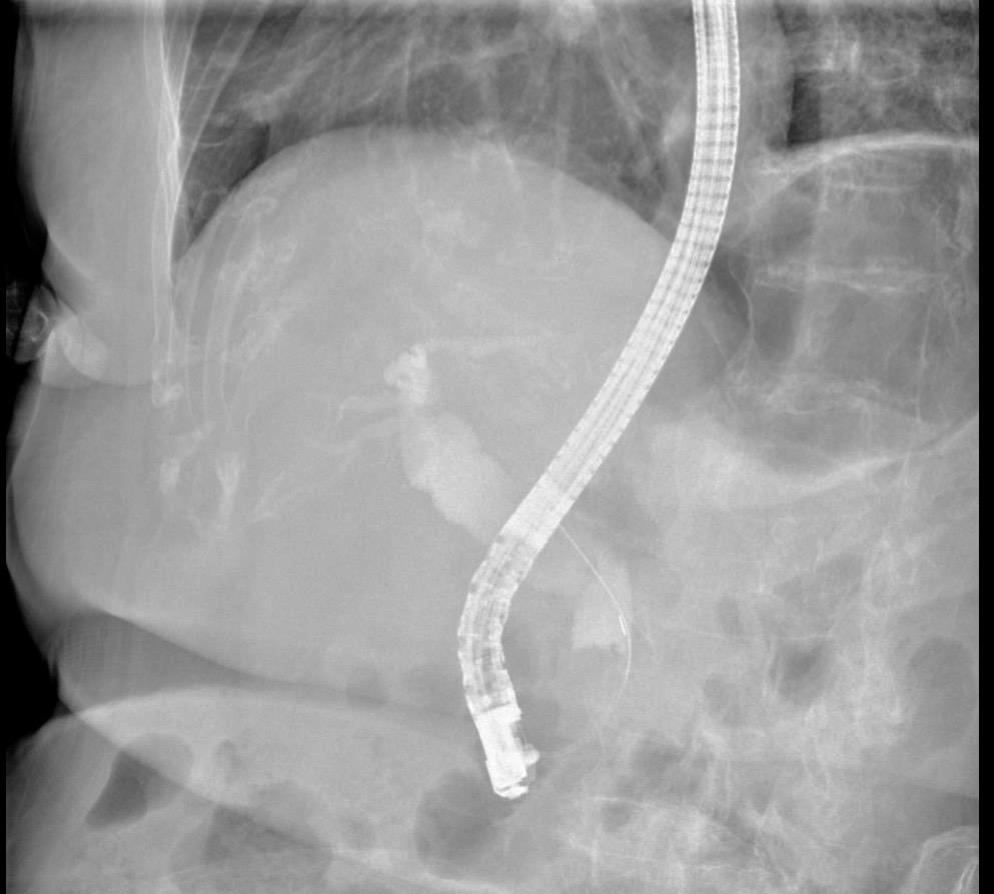

2026年的第一例ERCP,迎战完全梗阻胆管癌。 虽然辐射剂量远超胆管...